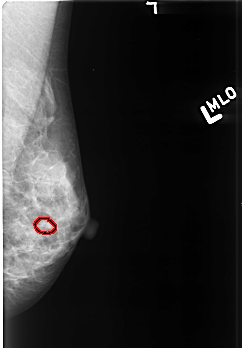

B_3418_1.LEFT_MLO

FILE: B_3418_1.LEFT_MLO.OVERLAY

TOTAL_ABNORMALITIES 1

ABNORMALITY 1

LESION_TYPE CALCIFICATION TYPE PUNCTATE-AMORPHOUS DISTRIBUTION CLUSTERED

ASSESSMENT 4

SUBTLETY 3

PATHOLOGY BENIGN

TOTAL_OUTLINES 1

BOUNDARY